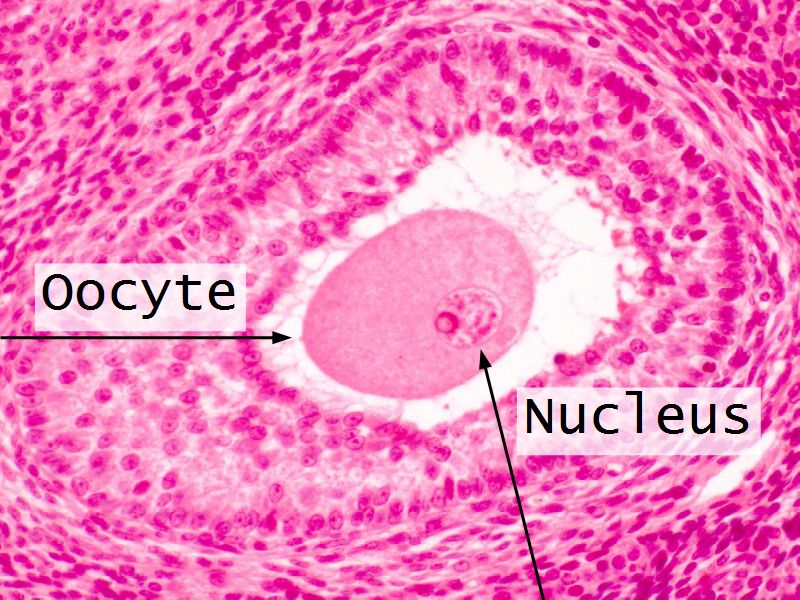

Components of a follicle

- Theca

- externa

- interna

- basal lamina

- Granulosa cells

- Antrum

- Cumulus oophorus >> Corona radiata

- Oocyte